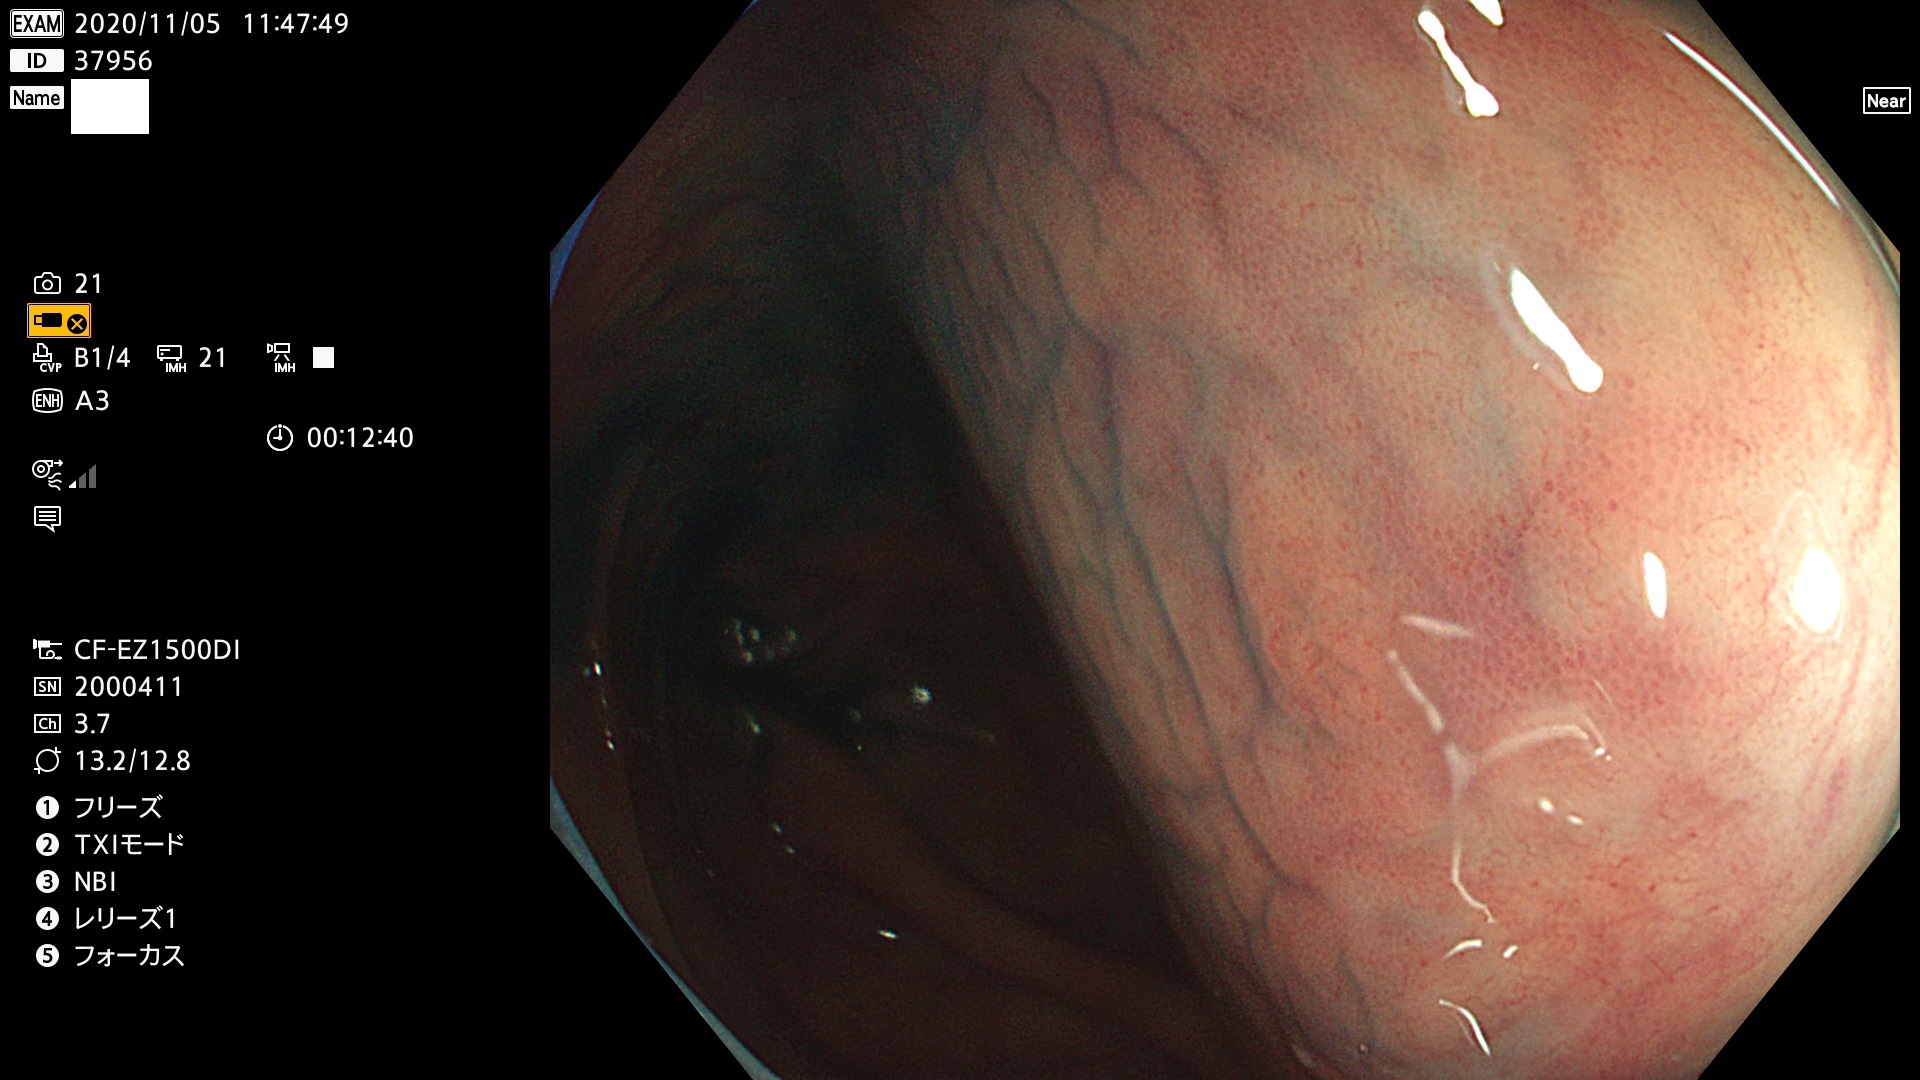

発見困難で危険性の高い平坦型病変(上記100名より抽出)

37900 37902 37903 37904 37905 37906 37907 37909 37910 37911 37912 37913 37914 37915 37916 37917 37919 37921 37922 37923 37926 37928 37929 37930 37931 37933 37934 37935 37936 37937 37938(SSAPのみ) 37939 37940 37941 37942 37943 37946 37947 37948 37949 37951 37952 37953(SSAPのみ) 37955 37956 37957(SSAPのみ) 37958(SSAPのみ) 37960 37962 37963 37964 37966 37967 37968 37971 37972 37973 37975 37976 37977 37979 37982 37983 37984 37985 37986 37987 37988 37989 37990 37991 37992 37993 37994 37995 37996 37998 37999